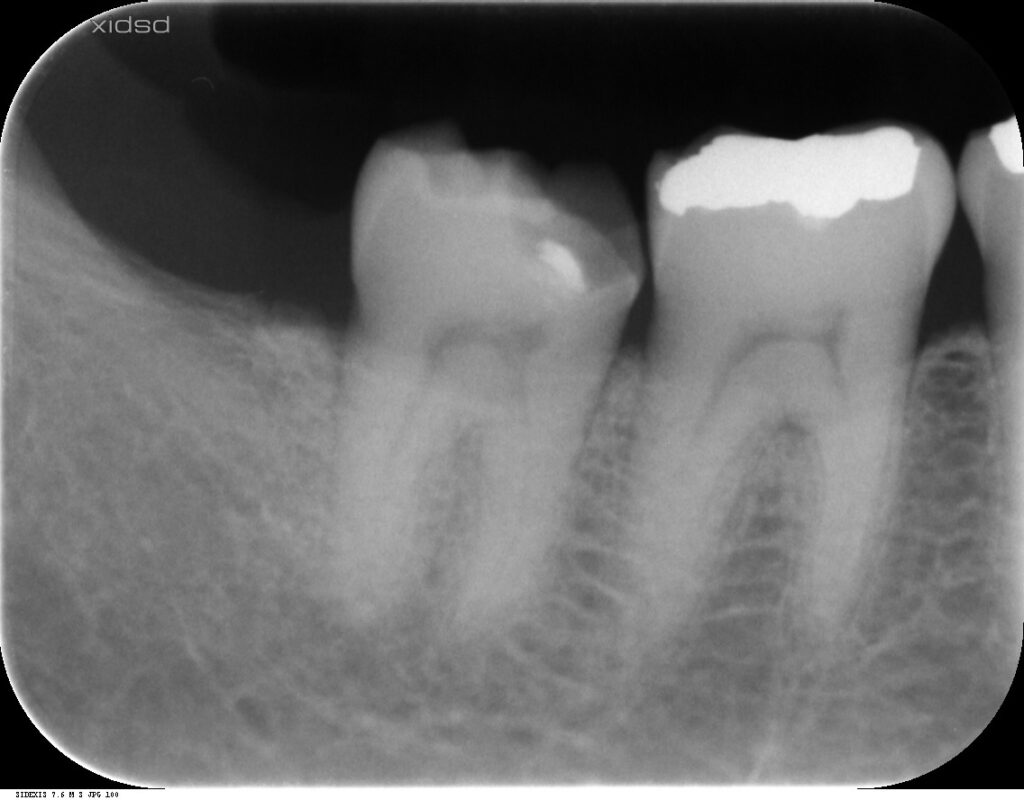

長年使っていた銀歯がある日突然外れることがあります。今回は、そんな主訴の患者様の症例です。

麻酔下で感染歯質を取り除き、裏装を兼ねてセメントを充填し痛みが出ないか経過観察を行った。

その後、生活歯であること、隣接歯をはじめ全顎的に咬耗があり、咬筋測定の結果、咬合力が強いことも考慮しゴールドアンレーを選択しました。